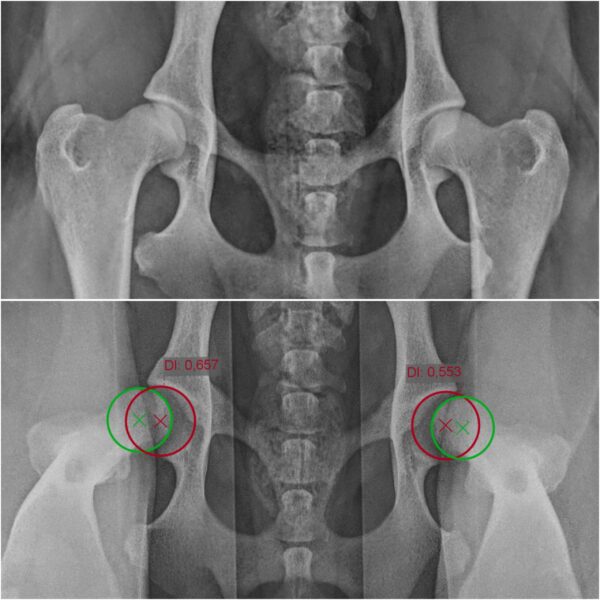

Narzędzie wspomagające ocenę luźności stawów biodrowych podczas badania ortopedycznego. Dystraktor wykorzystywany jest podczas diagnostyki dysplazji stawów biodrowych.